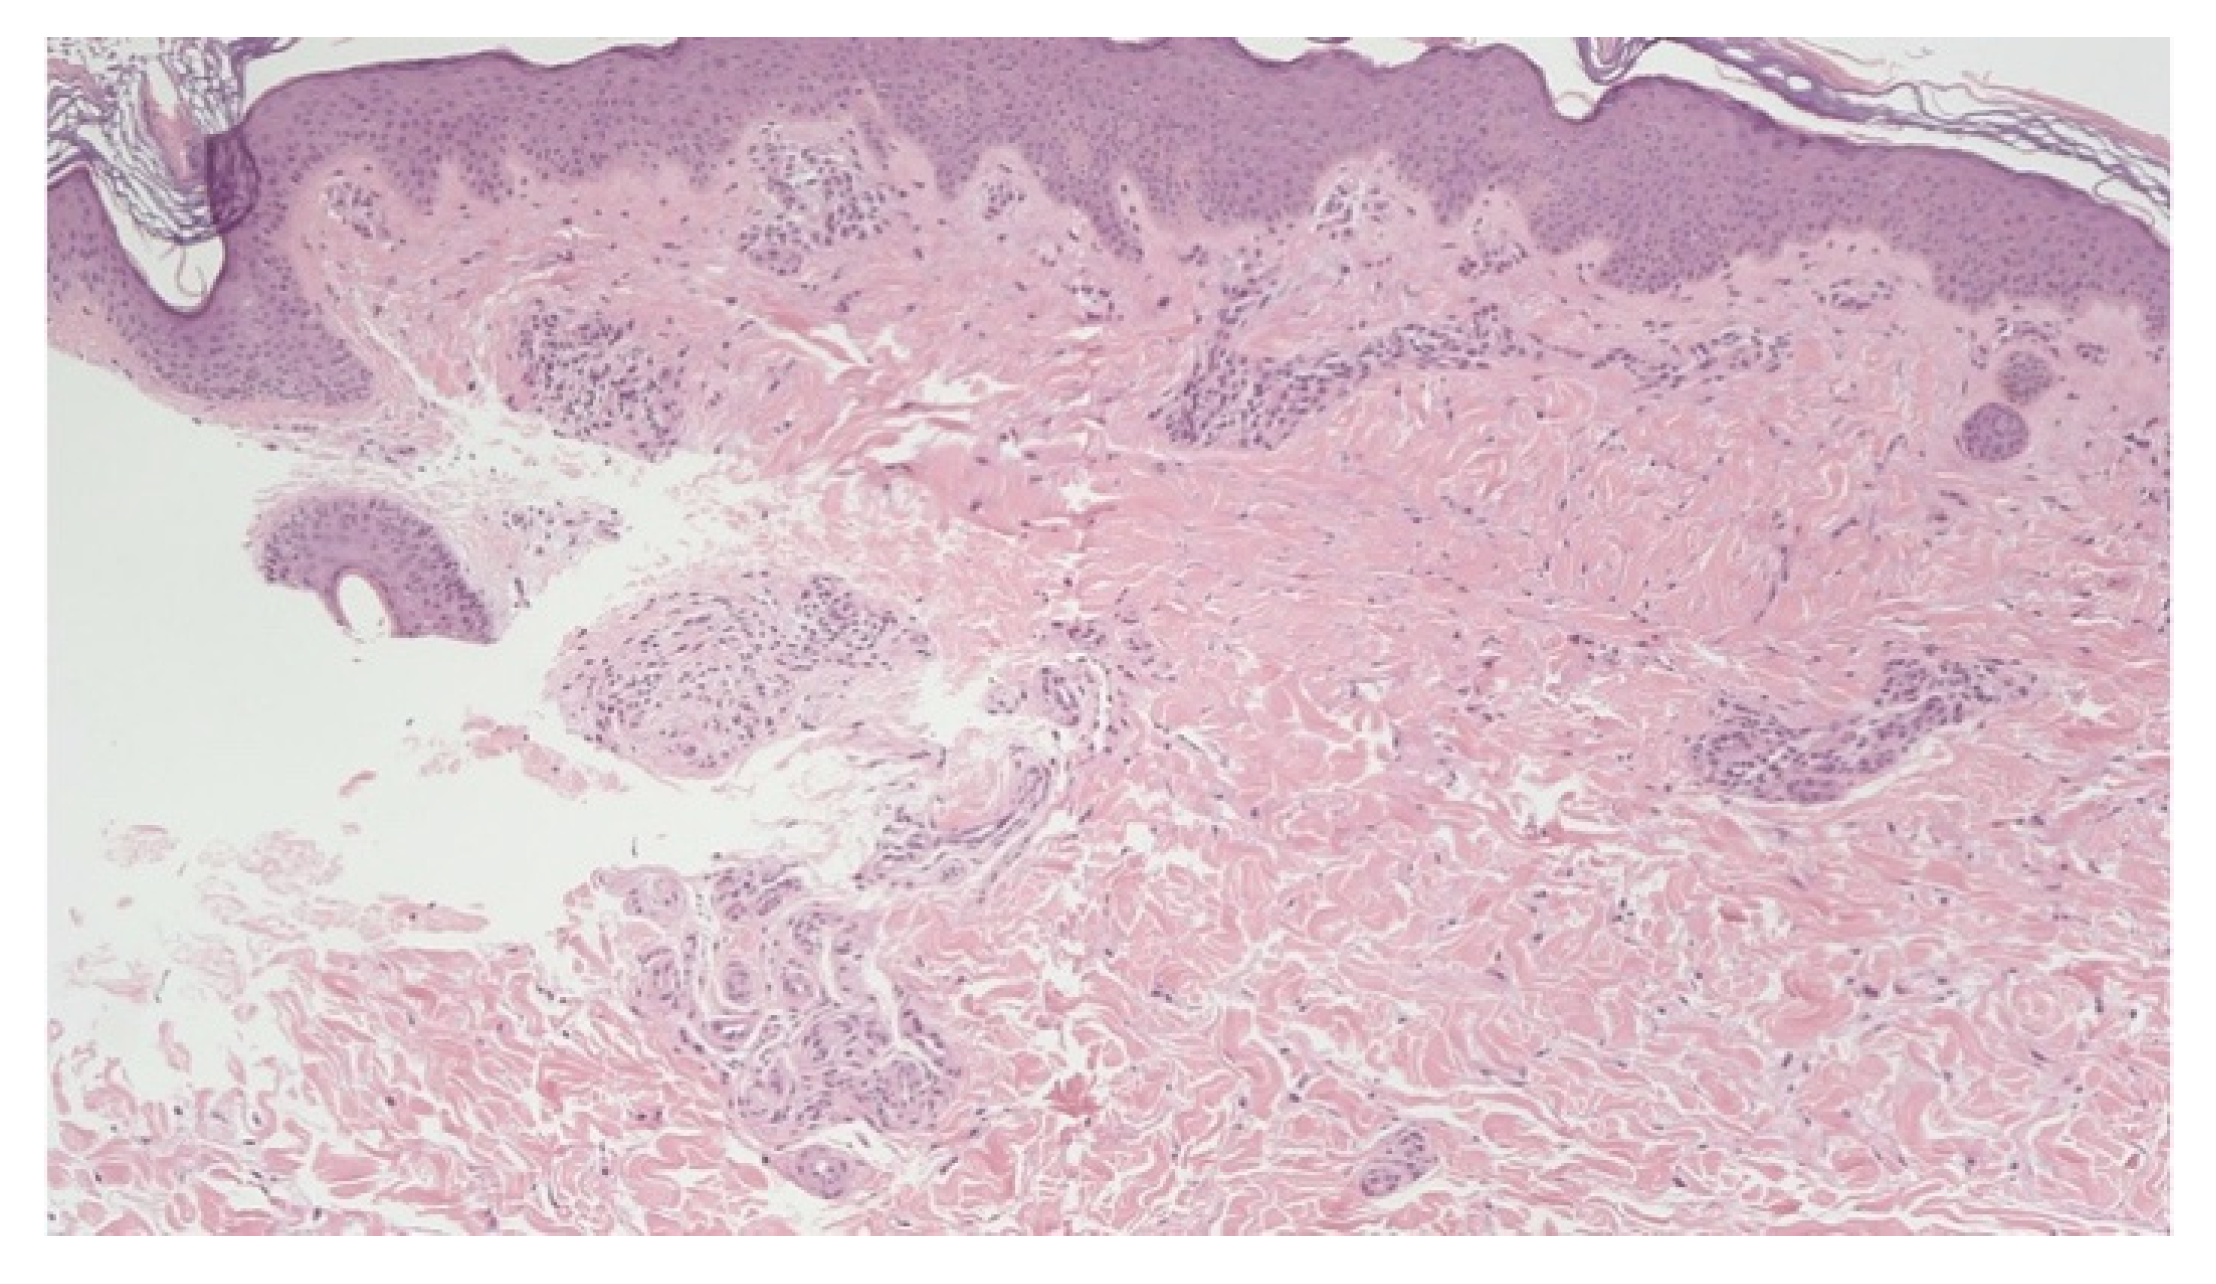

- Marušić, Z.; Korša, L.; Calonje, E. Dermal hyperneury. Clin. Dermatol. 2021, 39, 291–294. [Google Scholar] [CrossRef]

- Inaloz, H.S.; Kirtak, N.; Erguven, H.G.; Karakok, M.; Inaloz, S.S. Notalgia paresthetica with a significant increase in the number of intradermal nerves. J. Dermatol. 2002, 29, 739–743. [Google Scholar] [CrossRef]

- Ieremia, E.; Marušić, Z.; Mudaliar, V.; Kelly, S.; Rodriguez, P.G.; McNiff, J.M.; LeBoit, P.E.; Calonje, E. Expanding the clinical spectrum of dermal hyperneury: Report of nine new cases and a review of the literature. Histopathology 2019, 75, 738–745. [Google Scholar] [CrossRef] [PubMed]